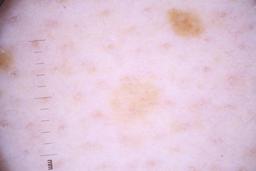

ISIC_4077341

Clinical

| Field | Value |

|---|---|

| acquisition_day | 1 |

| age_approx | 50 |

| anatom_site_1 | Trunk |

| anatom_site_2 | Anterior trunk |

| concomitant_biopsy | False |

| dermoscopic_type | contact non-polarized |

| diagnosis_1 | Benign |

| diagnosis_confirm_type | serial imaging showing no change |

| family_hx_mm | False |

| image_type | dermoscopic |

| lesion_id | IL_9238622 |

| patient_id | IP_1969685 |

| personal_hx_mm | True |

| sex | male |

Columns

Showing first 50 images.